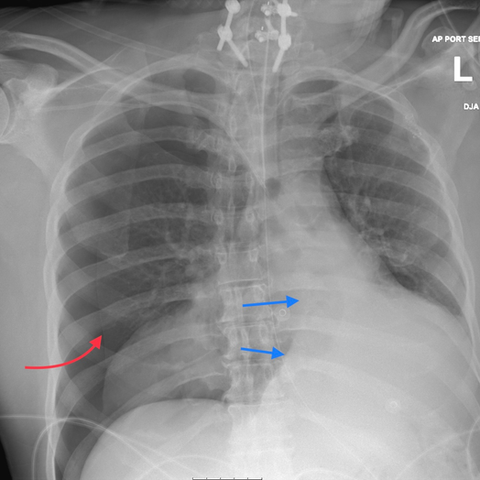

Plain X-rays

CT Scans